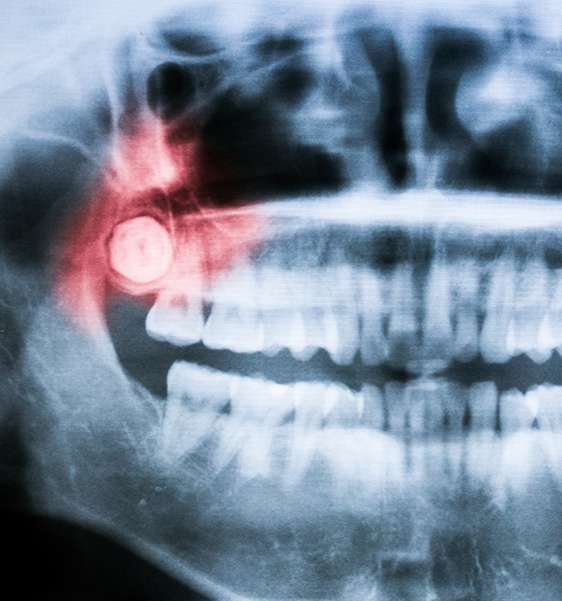

Wisdom teeth, also referred to as third molars, are the very last teeth to erupt through your gumline, typically between the ages of 16 and 24. While some people may only have one or two wisdom teeth, others can have all four or none at all. It’s important to note that not every wisdom tooth needs to be extracted. Dr. Mazhari can help determine whether allowing yours to grow in would compromise your oral health down the line by putting you at risk of developing a cyst, infection, or other complications. Call us today if you’re experiencing any pain or pressure in the back of your mouth that could be due to the need for wisdom tooth extraction in Alexandria.

- Precise Treatment Planning with Advanced Imaging

Your wisdom tooth extraction procedure can vary based on whether your third molars are impacted below the gumline or if they have fully erupted. For impacted teeth, we may refer you next door to the expert oral surgeon that we collaborate with to offer our patients outstanding results and truly professional care. This would involve the surgical removal of the wisdom teeth by creating a window in the gumline and removing them.